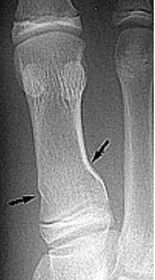

| What do the arrows show? | Stress fracture |

| Describe what has happened at the shaft of the 3rd met | Exuberant periosteal new bone production. May have resulted if a stress fracture was not treated and the patient continued weight bearing activities. |